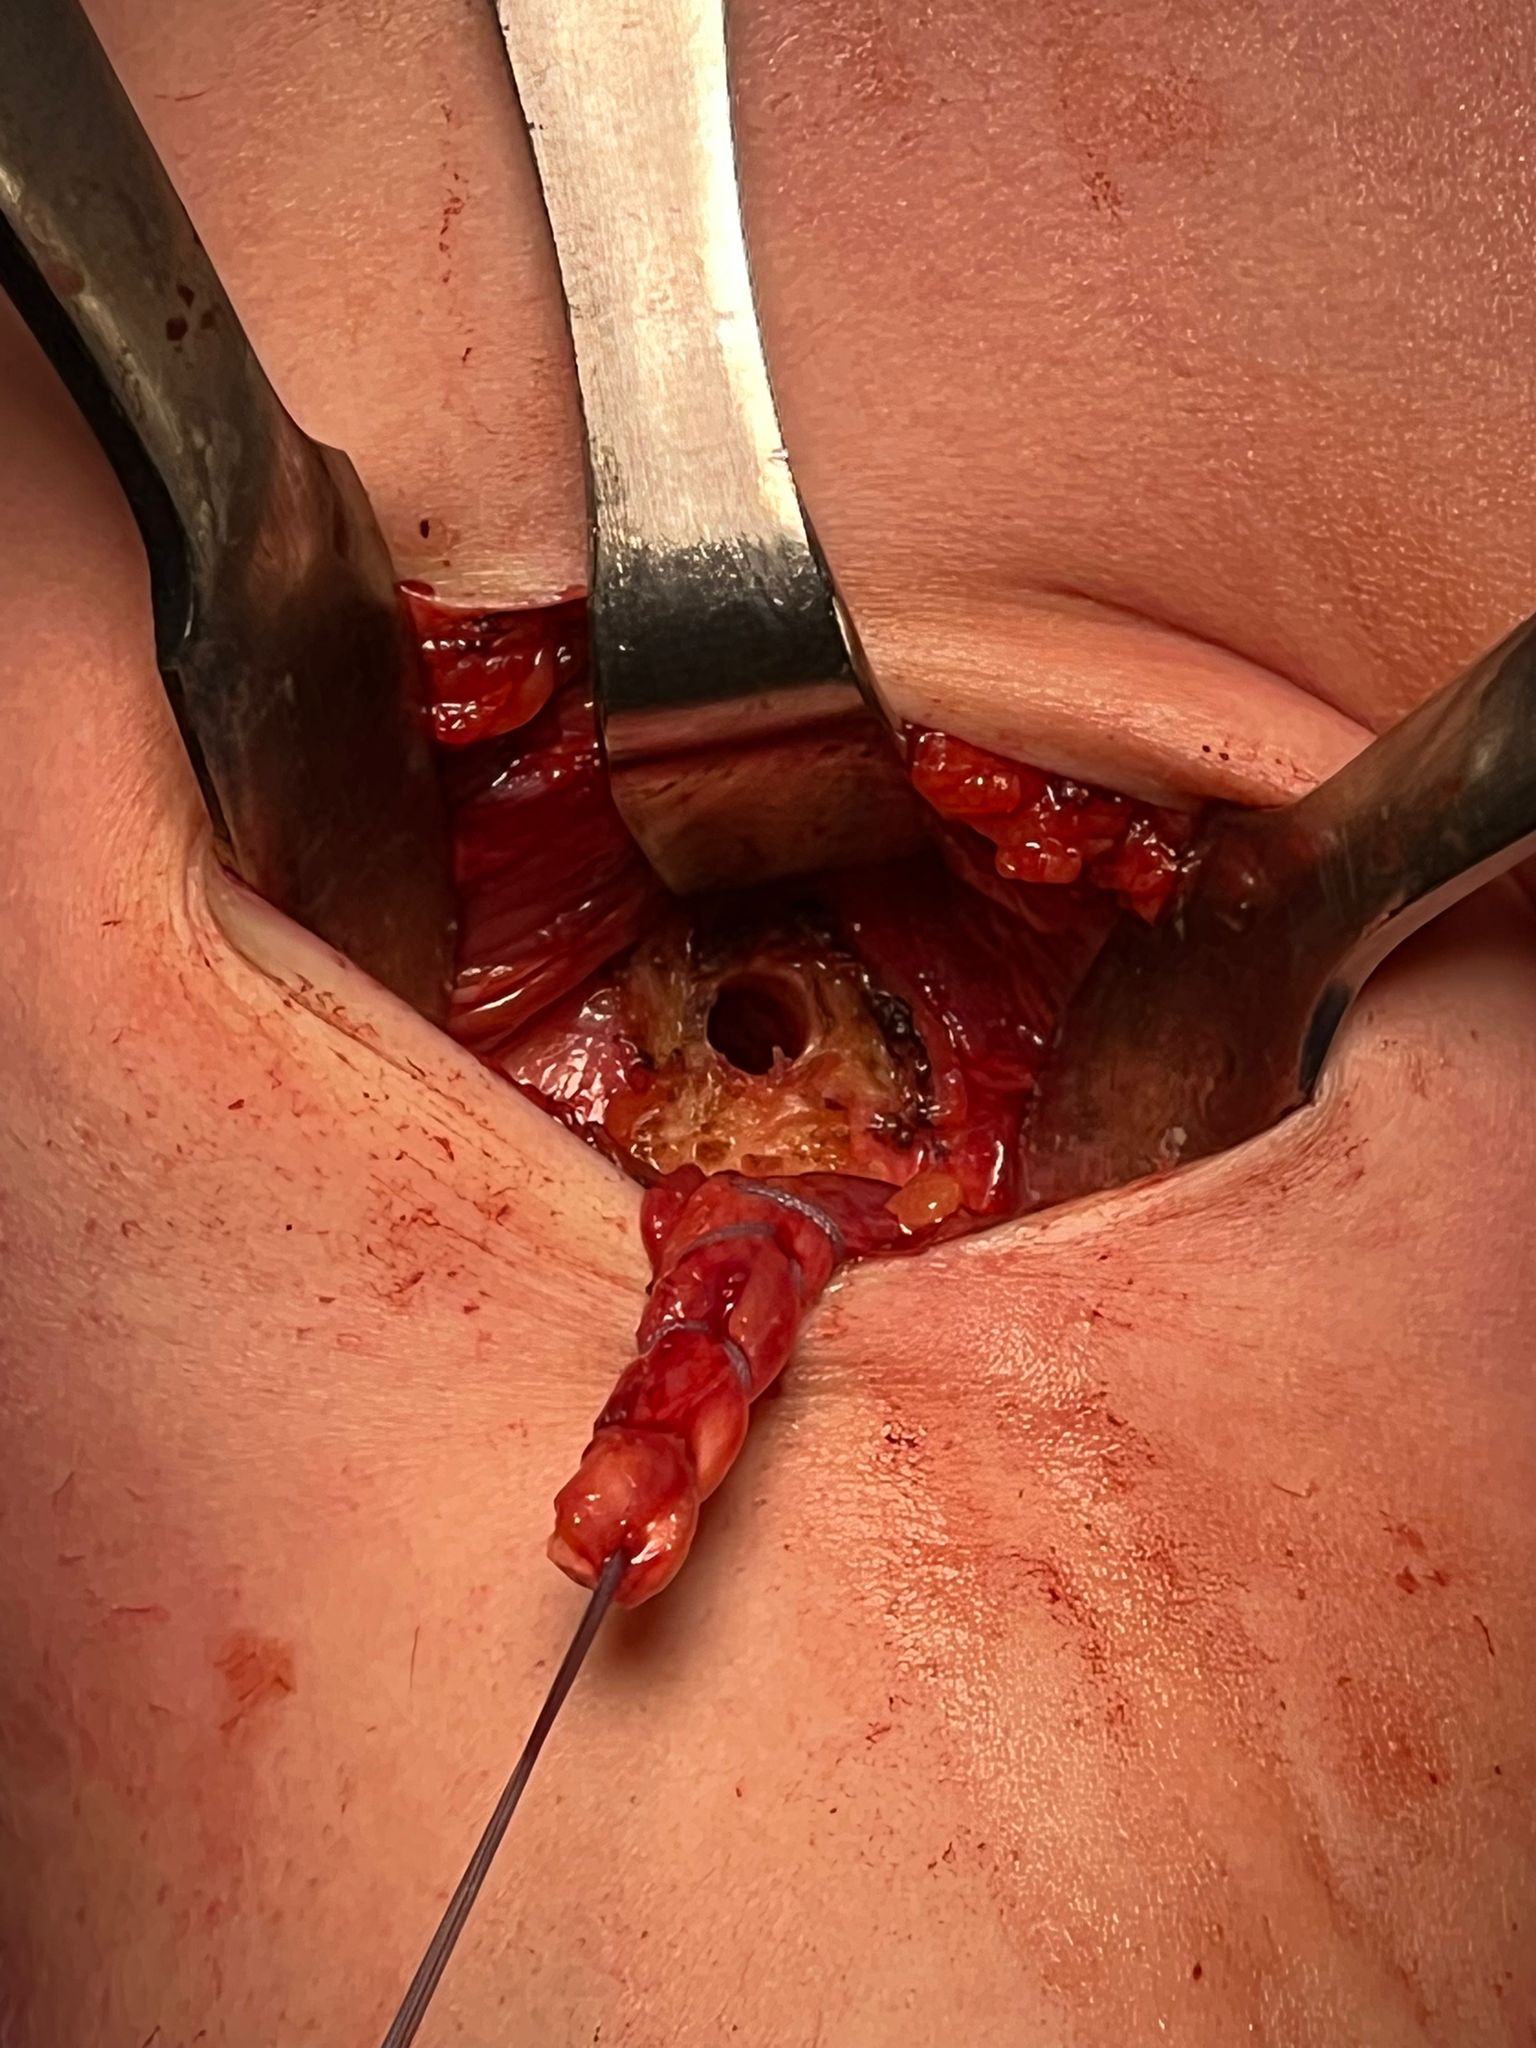

- incision centered on humerus below pectoralis tendon

- retract deltoid laterally / elevate pectoralis tendon / conjoint tendon medially

- find biceps tendon / shorten to 2cm of tendon / suture

- anchor biceps tendon

Bicortical open subpectoral biceps tenodesis using Arthrex Biceps Button